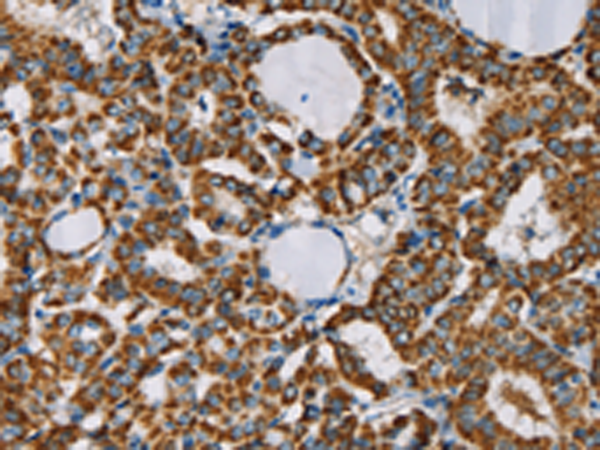

分类: 科研抗体货号: P08528别名: p8; C6.1B; MTCP1; MTCP1B; MTCP1NB; p8MTCP1应用: IHC反应种属: Human, Mouse